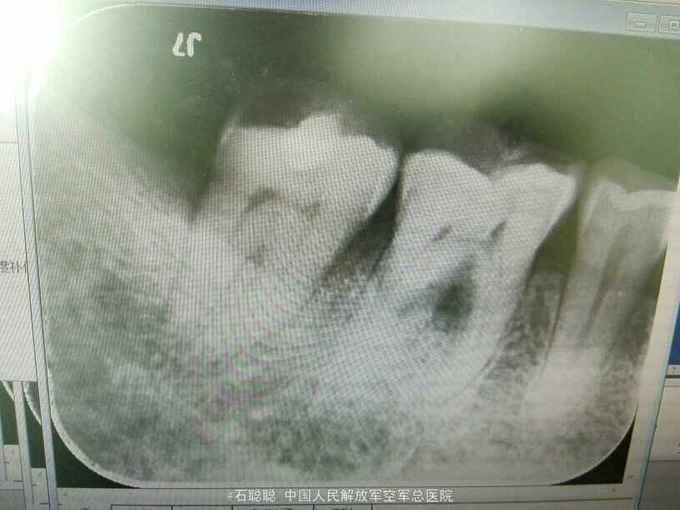

检查:右下7合面暂封物完整,探+,冷+,叩诊不适, 根尖片:右下7合面高密度充填影像,近髓,牙周膜根尖未见明显异常

诊断:右下7牙髓炎 治疗计划:右下7根管治疗后冠修复 处置:右下7“利多卡因”阻滞麻醉下,去除暂封,开髓,揭顶,探及近舌,近颊,远中3个根管口,疏通根管,见中等量血性渗出,冲洗,干燥,置失活剂,氧化锌暂封 一周后复诊:去除右下7暂封,测工作长度,近舌=17mm,扩大至30#,近颊=远中=16mm,扩大至35#,冲洗,干燥根管及髓腔,置CP棉球,氧化锌暂封 一周后复诊: 查:右下7叩痛-,不松动,氧化锌完整在位 处:去除右下7氧化锌暂封,试主尖,冷侧压充填,氧化锌暂封 一周后复诊:右下7氧化锌完整在位,叩痛-,不松动 处置:右下7颊、舌、近中、远中壁高度厚度均大于2mm,磷酸锌垫底,树脂充填,钴铬金属全冠预备,平齐龈缘肩台,取模,比色A3.5 一周后复诊:试戴右下7钴铬烤瓷冠,调合,粘固 医嘱:勿用患牙咀嚼硬食 不适复诊